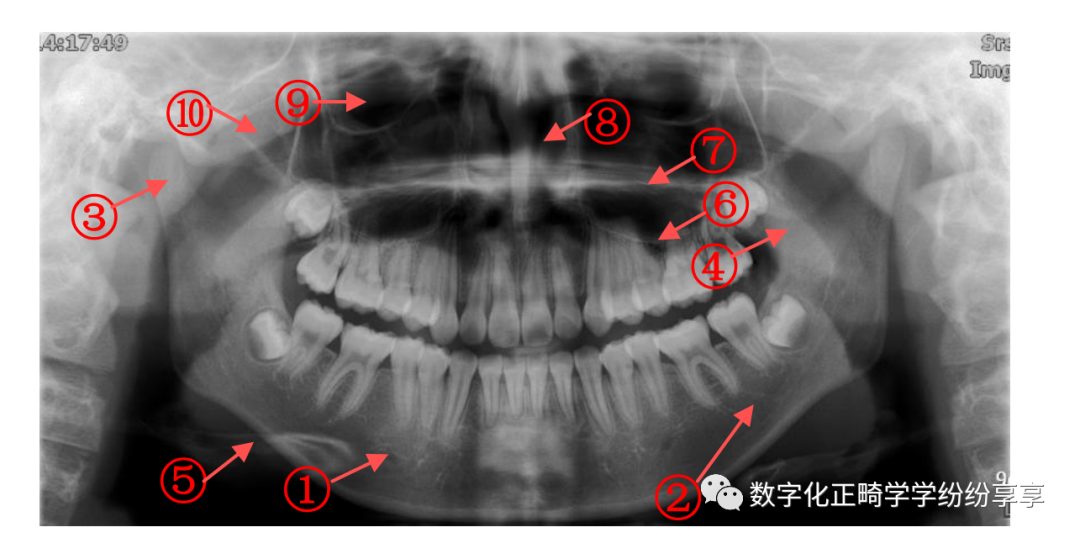

1) 优点:显示上下颌骨全貌:颌骨形态、牙齿发育、全口牙周病牙槽骨吸收情况、颌骨病变及骨折等。

2) 下颌骨特点:把马蹄弓形的上下颌骨展为平片;骨皮质厚薄不一但光滑连续(对比骨折);骨松质纹理水平;髁突形态多样;下牙槽神经管的特点(分叉位臵多样)。

拍摄全口牙齿,二维成像 ,便于医生快速、全面的掌握患者牙齿情况,如儿童牙齿发育情况(根尖闭合情况等)、成人牙周情况。

①颏孔 ②下颌管 ③髁突 ④喙突 ⑤舌骨 ⑥上颌窦底 ⑦硬腭 ⑧鼻腔 ⑨眼窝 ⑩颧弓